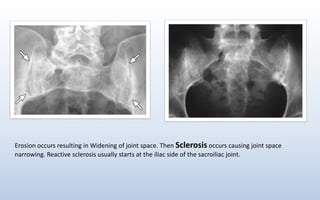

Erosion occurs resulting in Widening of joint space. Then Sclerosis occurs causing joint space

narrowing. Reactive sclerosis usually starts at the iliac side of the sacroiliac joint.

Erosion occurs resultingin Widening of joint space. Then Sclerosis occurs causing joint space narrowing. Reactive sclerosis usually starts at the iliac side of the sacroiliac joint.